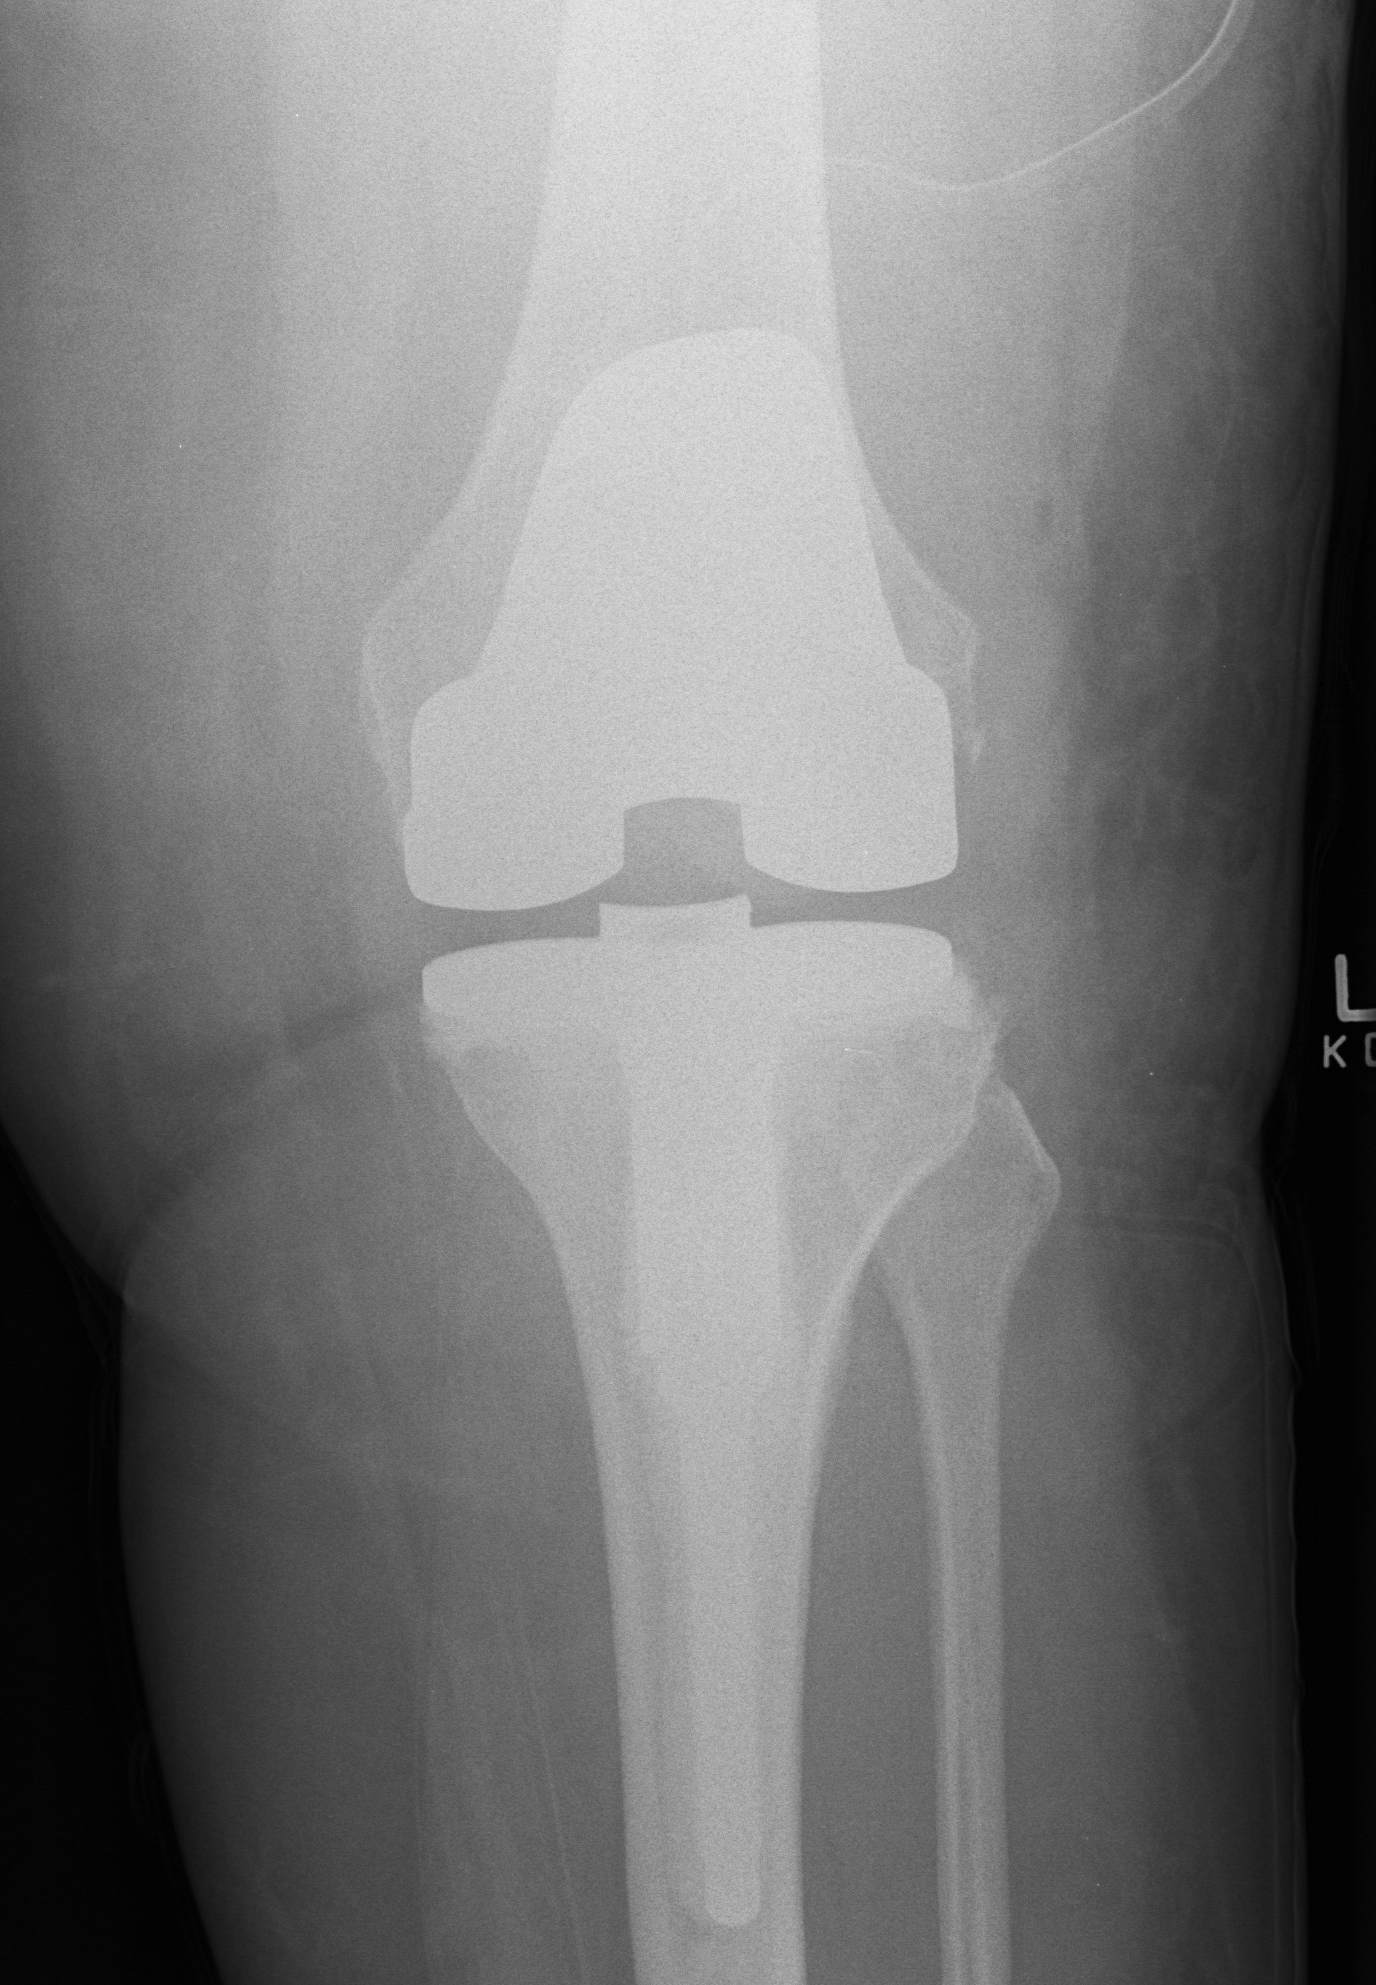

B. Tantalum cones metaphyseal filling / Trabecular metal

Meneghini et al JBJS Am 2009

- tantalum porous tibial implant in 15 pateints followed average 3 years

- AORI type 3 and type 2B

- knee society score average 85

- all had evidence osteointegration, no loosening

C. Mesh + impaction bone grafting

D. Tumour prosthesis / Custom implants